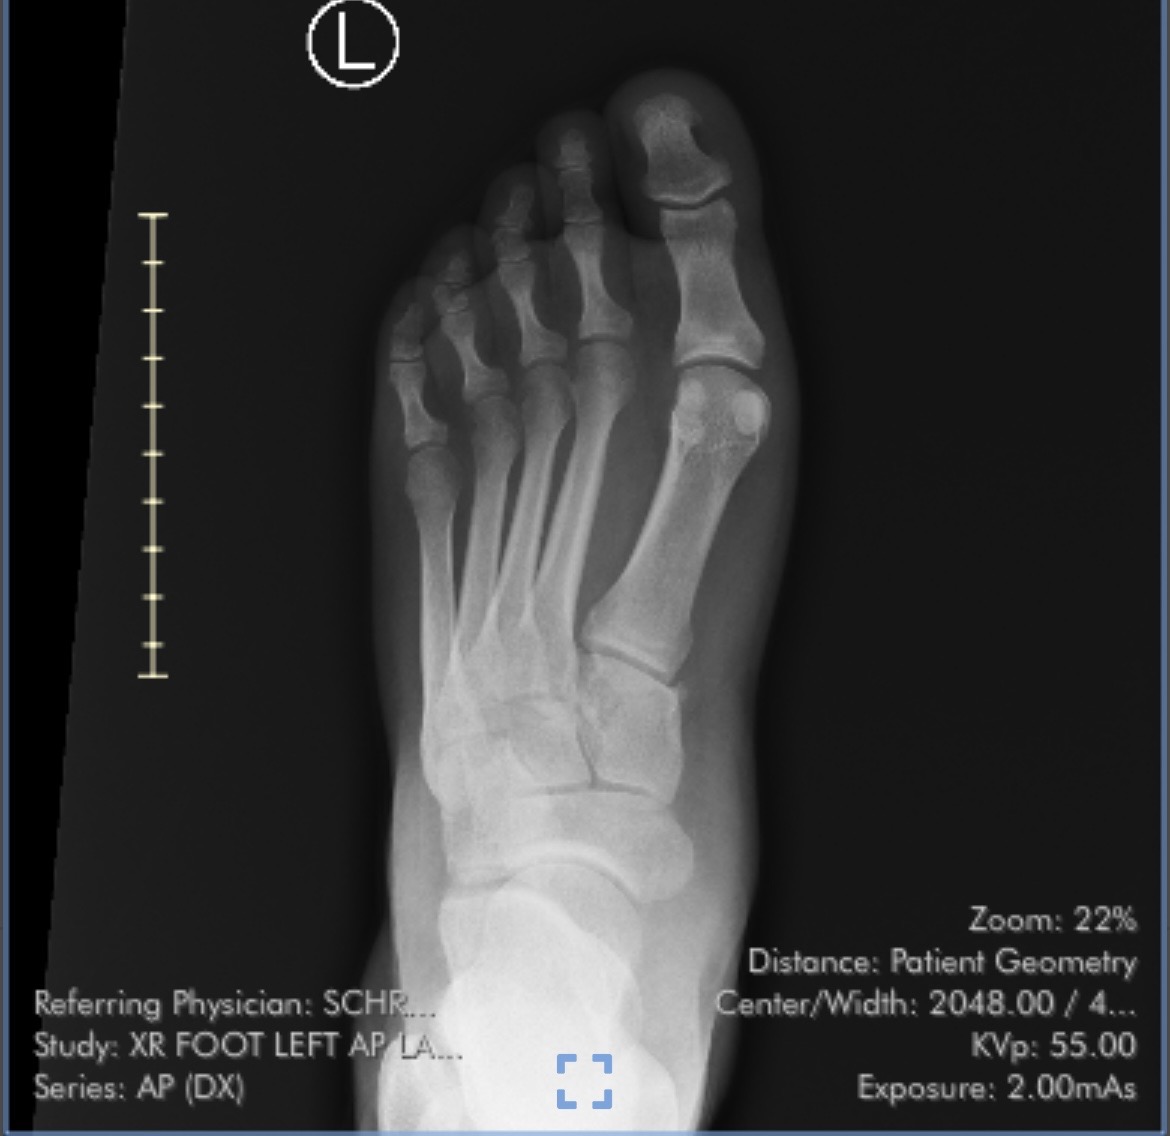

Our good friend Indigo is in need of our help to pay for a much needed surgery for a Lisfranc ligament tear and fracture in their left foot. They work on their feet as a server to pay their bills and can’t continue to work without medical care. Indigo has applied for Medicare but has been denied four times this year, so this surgery will be extremely expensive to pay for out of pocket. They also need support to cover housing while they are unable to work as much, as they’ll need 6-12 months of recovery after the surgery. Indigo is the one of the kindest and most generous people you will ever meet, giving to others and lending a hand without a second thought. They are more than deserving of your help. Please help us support our friend during this difficult time!